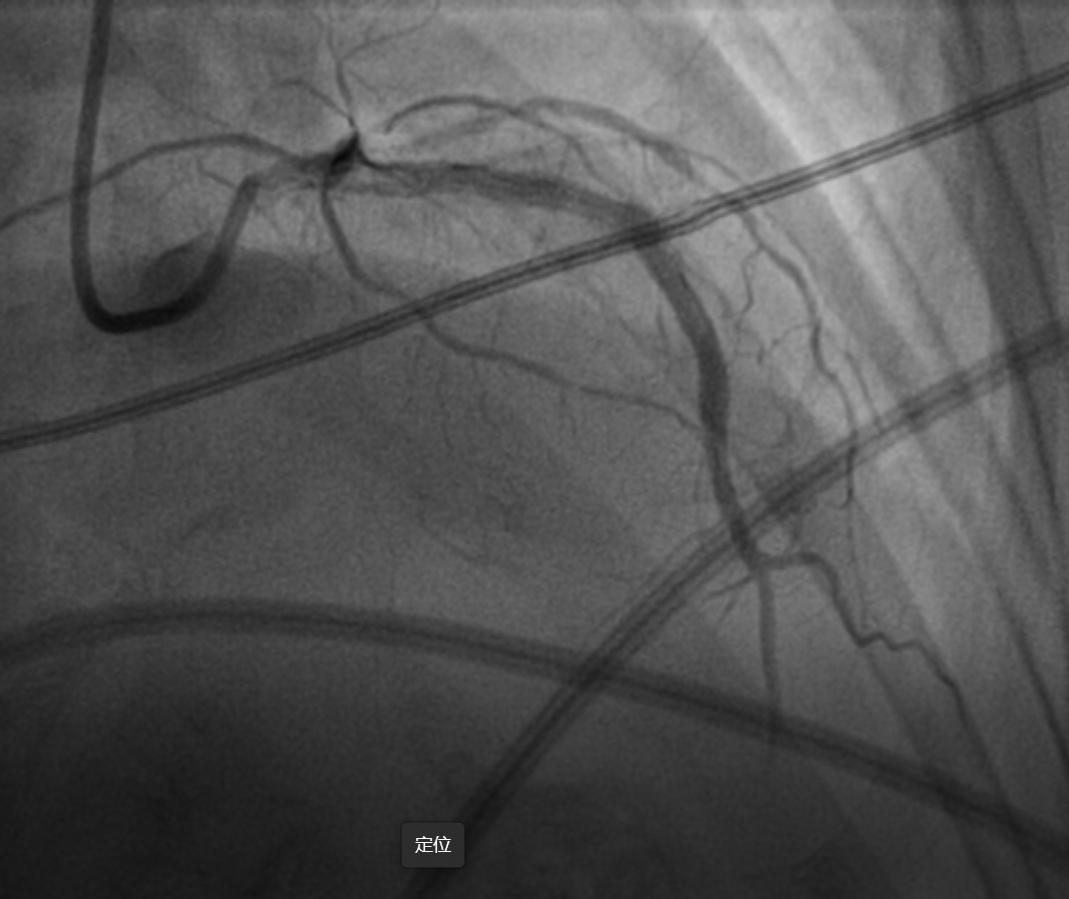

经1.5mm旋磨头旋磨8次后,旋磨头不能完全通过病变,而且患者出现顽固性无复流,经微导管多次给与腺苷、硝普纳以及欣维宁后前降支血流有所改善,但效果不明显,前壁导联心电图ST段抬高。随后使用2.5mm球囊到达病变后,多次加压扩张难以使钙化狭窄的部位充分扩张,立即使用Shockwave冲击波球囊行碎石手术。经过8个周期(80个脉冲)冲击波治疗后,IVUS证实钙化病变出现断裂,最终成功植入支架,达到理想的支架膨胀贴壁效果。

支架植入术后影像